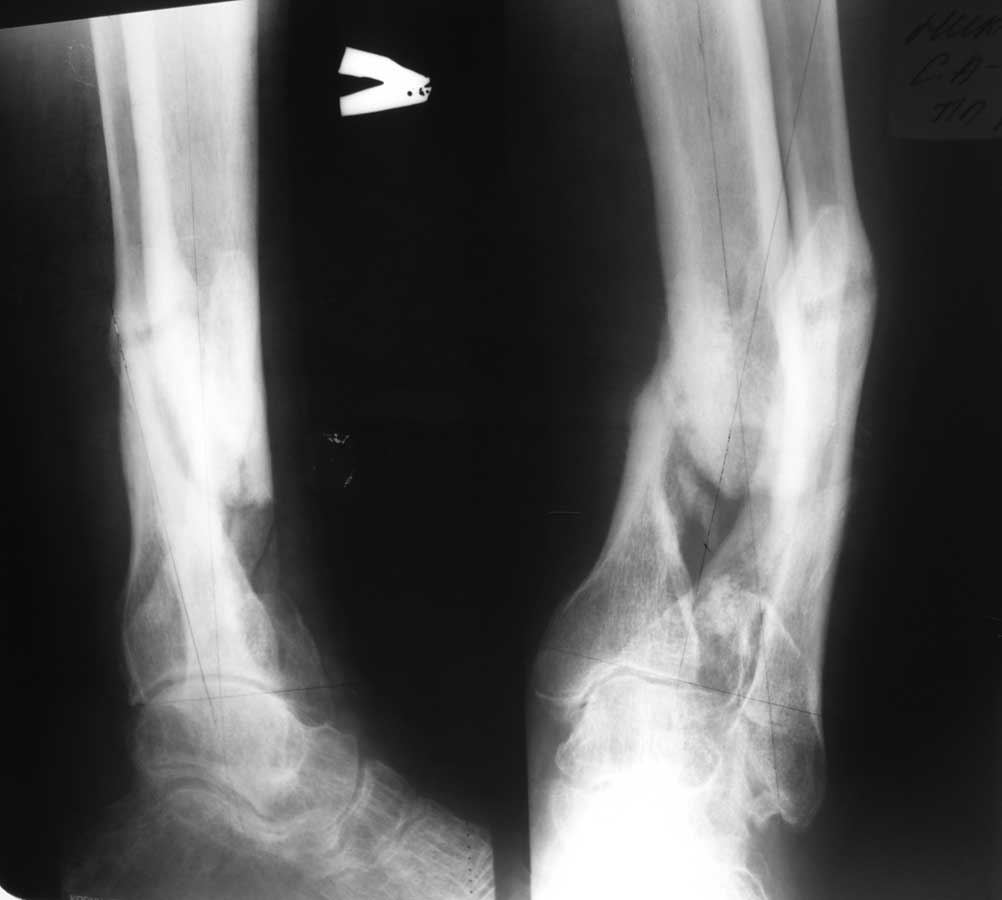

А можно увидеть для начала не 3D, а стандартные рентгенограммы (фас и профиль)?

Уважаемый Александр Николаевич! Вот фото рентгенограмм.